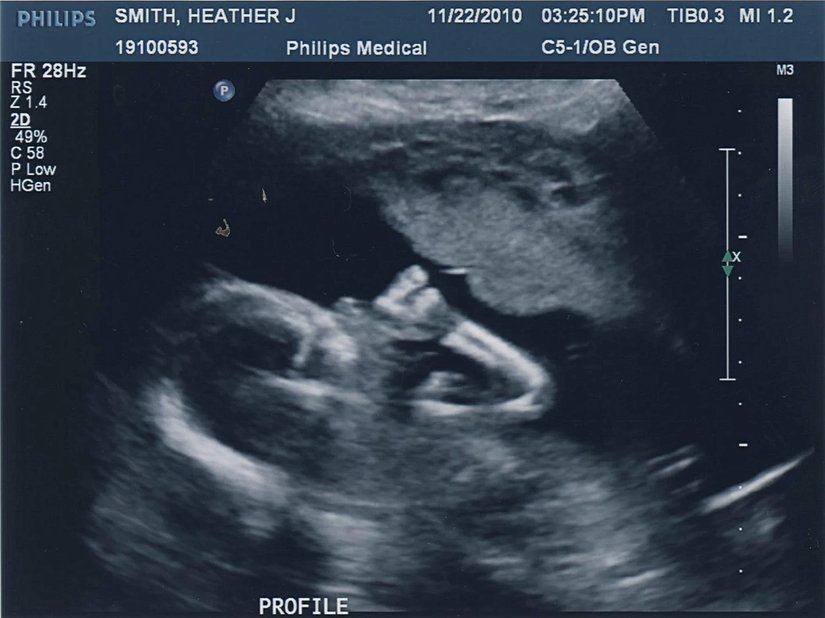

Araştırmacıların yaptığı literatür taramasına göre el tercihi, gebeliğin 13. haftası gibi erken bir dönemde bile tespit edilebilir olmaktadır. Makalede uzmanlar şöyle yazıyorlar:

Gelişimin 13. haftasında omurilik, motor korteks ile fonksiyonel olarak bağlı değildir; çünkü kortikospinal projeksiyonlar 15. haftadan erken anteriyör omuriliğe bağlanmaz.

Bunu tespit etmenin yolu, bebeklerin ana rahmindeki parmak emme davranışlarını ultrason ile takip etmektir. Bu görüntülerdeki el tercihi, doğum sonrasındaki el tercihi ile kıyaslanır ve ikisi arasında güçlü bir ilişki bulunabilirse, el tercihinin beyin gelişiminden (ve hatta omuriliğin beyne bağlanmasından) çok önce belirlendiği tespit edilebilir. Yapılan araştırmalar, gerçekten de durumun böyle olduğunu göstermektedir!